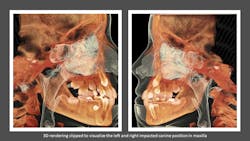

Cone Beam Computed Tomography (CBCT) has specific and unique diagnostic benefits in orthodontics including the assessment of tooth location and position, stage of development and status of adjacent teeth. CBCT enables the clinician to be able to evaluate anomalies in dental position, such as impactions and ectopic teeth, where it brings significant value to diagnosis and treatment planning.

In this clinical case, a patient with impacted maxillary canines was re-evaluated using an i-CAT FLX from KaVo Imaging (manufactured by Imaging Sciences International LLC) The 3D views allowed for better determination of the clinical status of the patient by bringing more clarity to the labiolingual relationships of the impactions and the identification of any associated complications, such as root resorption in adjacent incisors.